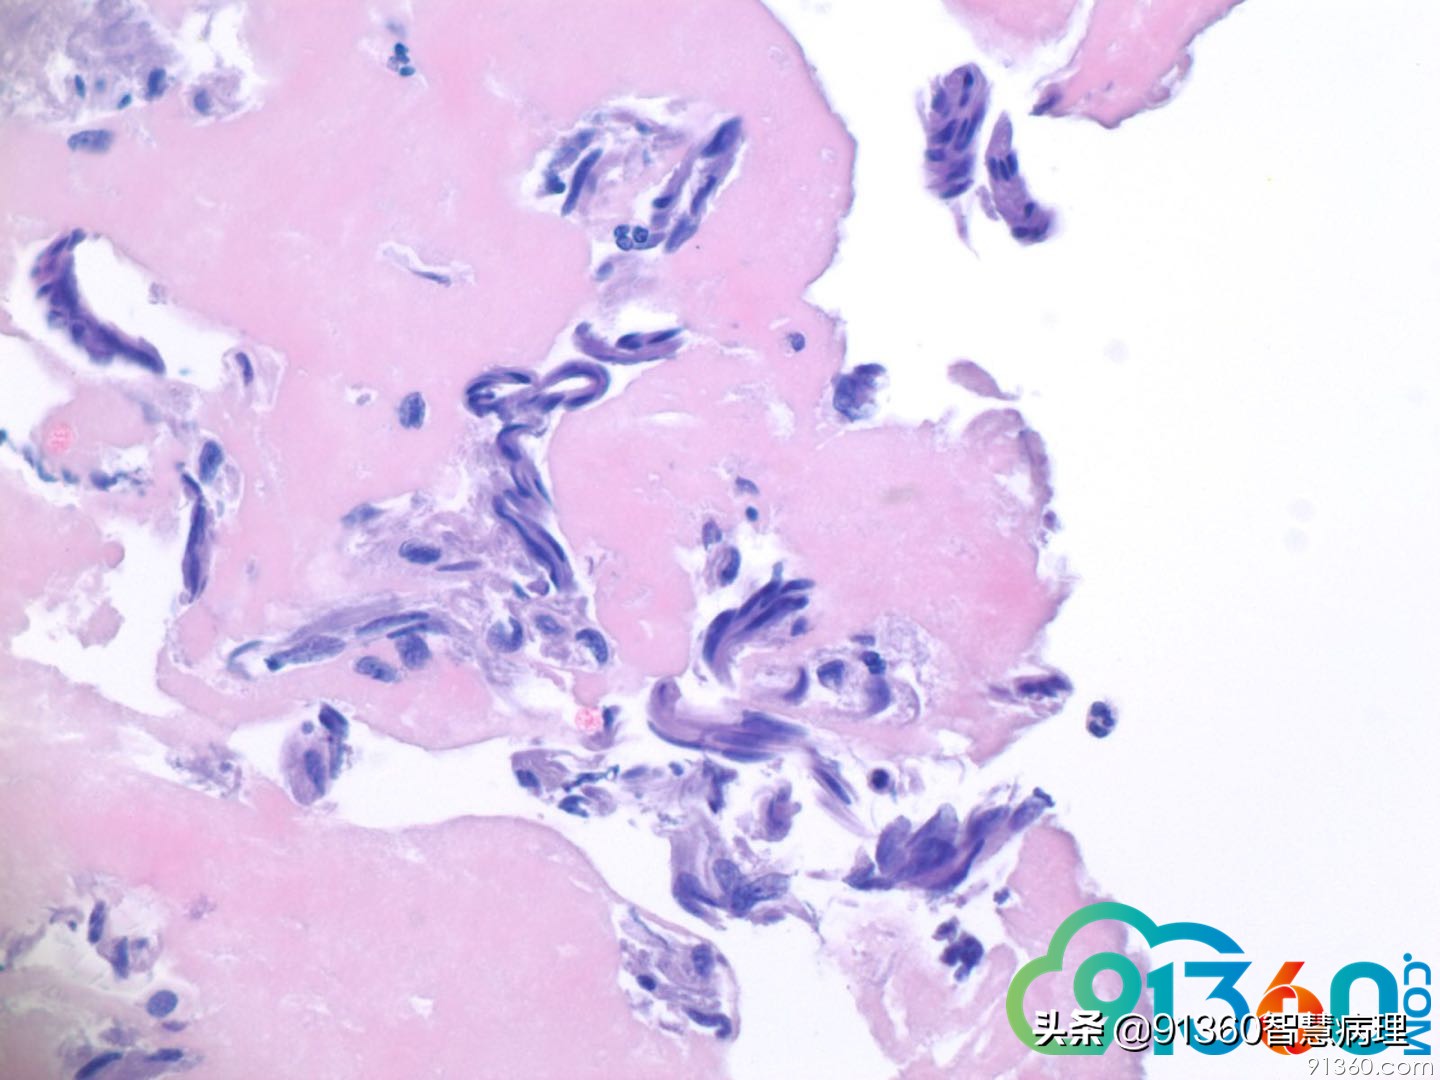

赵澄泉 70多岁,在过去四年HPV持续阳,几次Pap LSIL, ASCUS, 活检CIN 1。现查Pap test双查高危HPV阳性怎么发报告? 孙煜昀 和上次发的角化型鳞癌一模一样,表层角化不全。不发高级别疑癌显得我太怂了,不过要签字,我还是发AH 宋晓华 狂魔乱舞,张牙舞爪的样子,看起来不善良呀ASCH 阎培莎 我个人认为和最近赵老师发的那个病例不一样!细胞形态特征上有区别,年龄上那个病人是50多岁(年轻20 岁)。 这一例细胞不典型不明显(虽然有很多核梭性)并也沒有那么多的stromal 角化物质 。单纯以上照片诊断SCC 很难。萎缩不是不可能,但是如果是atrophy ,赵老师为什么又在这里show 呢?从实际工作的角色上讲,叫ASCUS plus HPV 阳性和叫 ASC-H 结果是一样的!都是end up with biopsy 王瑞辉 持续的HPV感染无进展,萎缩的停滞的低度或高度病变,定期复查高龄的妇女有些这种情况 石丽华 高级别 赵澄泉 此例细胞技术员叫鳞癌,为此我让技术室用剩余PAP 液体做了个细胞块, 如下图9-13现在应该报啥? 赵海鸥 高级别,不排外浸润 郭滟 平常不怎么看细胞学,但感觉问题不大啊 赵澄泉 @阎培莎 除了细胞病理专家外,你也是一很好的心理医生 郭晓静 hr~hpv阳性。游离高级别上皮内病变。 阎培莎 细胞pap 和细胞块HE 染色非常一致。To me this is atrophy! it isn’t in uncommon for 年长的妇女with 持续HPV positivity ( 许多妇女HPV 阳性不是HPV 17/18 而是other types ,后者时常不是那么的indicative!) . @赵澄泉UPMC 我做住院医师时inhospital exam 都是考了600+ 分!比我们那年的National scores 高出去200 多分!(我比较会“猜题”,考虑到最常见的情况应该是什,出考题的人想让要我们怎么回答)我纠正一下:细胞pap 和细胞块HE 染色非常一致。To me this is atrophy! it isn’t uncommon for 年长的妇女with 持续HPV positivity ( 许多妇女HPV 阳性不是HPV 16/18 而是other types ,后者时常不是那么的indicative!) . @赵澄泉UPMC 姜锦贵 萎缩 张杰 @郭滟 瑞金医院 我和您感觉一样 何长青 @赵澄泉UPMC 我看是萎缩的细胞,没问题!这样的细胞每天都会遇到 张杰 有了细胞块,可以做组化了。估计赵老师有免疫组化结果 李娟 赵老师,您这个病例看上去核比较温和呢但有的图核有些拉长细胞块不太支持高级别,但是hpv持续阳性,核有点异型 赵澄泉 Ki67, p16

赵澄泉 形态学和免疫都支持一定无高级或癌。昨天很放心的发了ASCUS.这个病例说明有时利用残余液基做个细胞块还是有用的。 张杰 @赵澄泉UPMC 谢谢赵老师,您这个病例细胞学还是挺吓人的,细胞块细胞形态就善良多了。细胞块确实可以解决很多问题 赵澄泉 如你有兴趣,可以比较这个病例与上边我发的那例不典型parakeratosis, 活检下面为鳞癌,这二例细胞学特佂是不同的。本例报ASCUS,萎缩还是比较合适的。病人应该不会有癌。anyway, ASCUS HPV positive, patient should have Colposcopy Thank you all for the discussion. Good night. Here is Friday morning. Will start to work 阎培莎 Thanks for sharing! 还是那句话: 赵老师自己花了时间让大家学习了!@赵澄泉UPMC 李娟 但是赵老师我们有时也做细胞块,但没有您做的这么好 张杰 赵老师这个鳞癌病人的液基有角化细胞,细胞有异性。@赵澄泉UPMC 谢谢您的分享

何长青 卵巢切除后的萎缩病例,常见赵老师给出的病例形态特点,核虽说有扭曲拉长,但是核染色质是温和的! 孙煜昀 @赵澄泉UPMC 好病例,学习到了